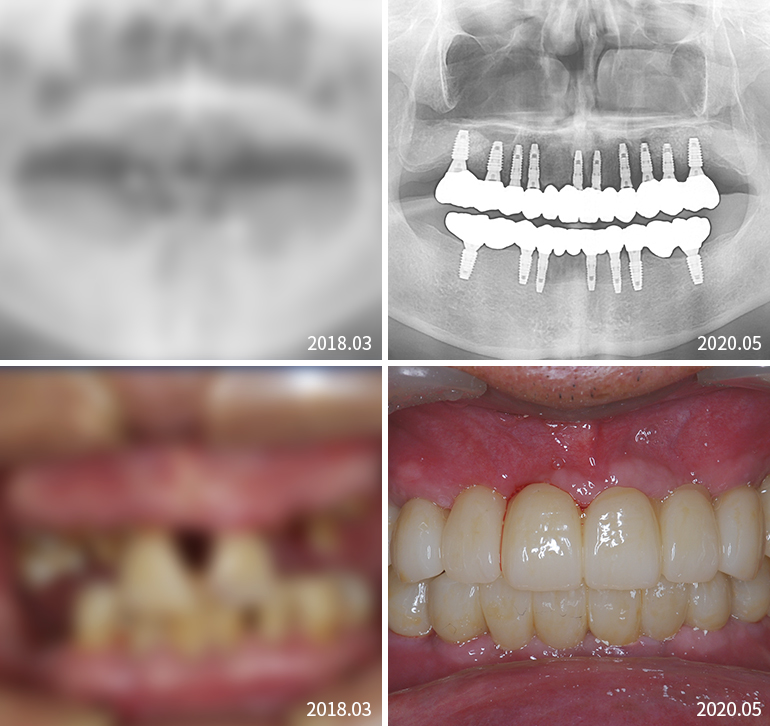

전체임플란트